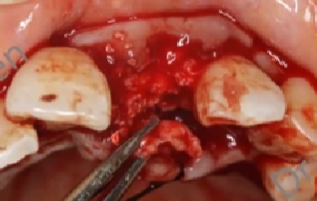

像下图中的这类缺损,临床上很多见,尤其是颊侧骨板缺失3-6mm左右,遇到这类病例是非常头痛的。

-

对于比较厚的牙龈,我们可以做一些即刻的GBR,但是不进行即刻的修复。

对于一些薄型的牙龈,我们往往会采用一些植骨方法,进行延期种植。

下图显示牙槽骨的几种缺损形态。左边和右边没有争论,中间这类最多见,也是比较有争论性的。